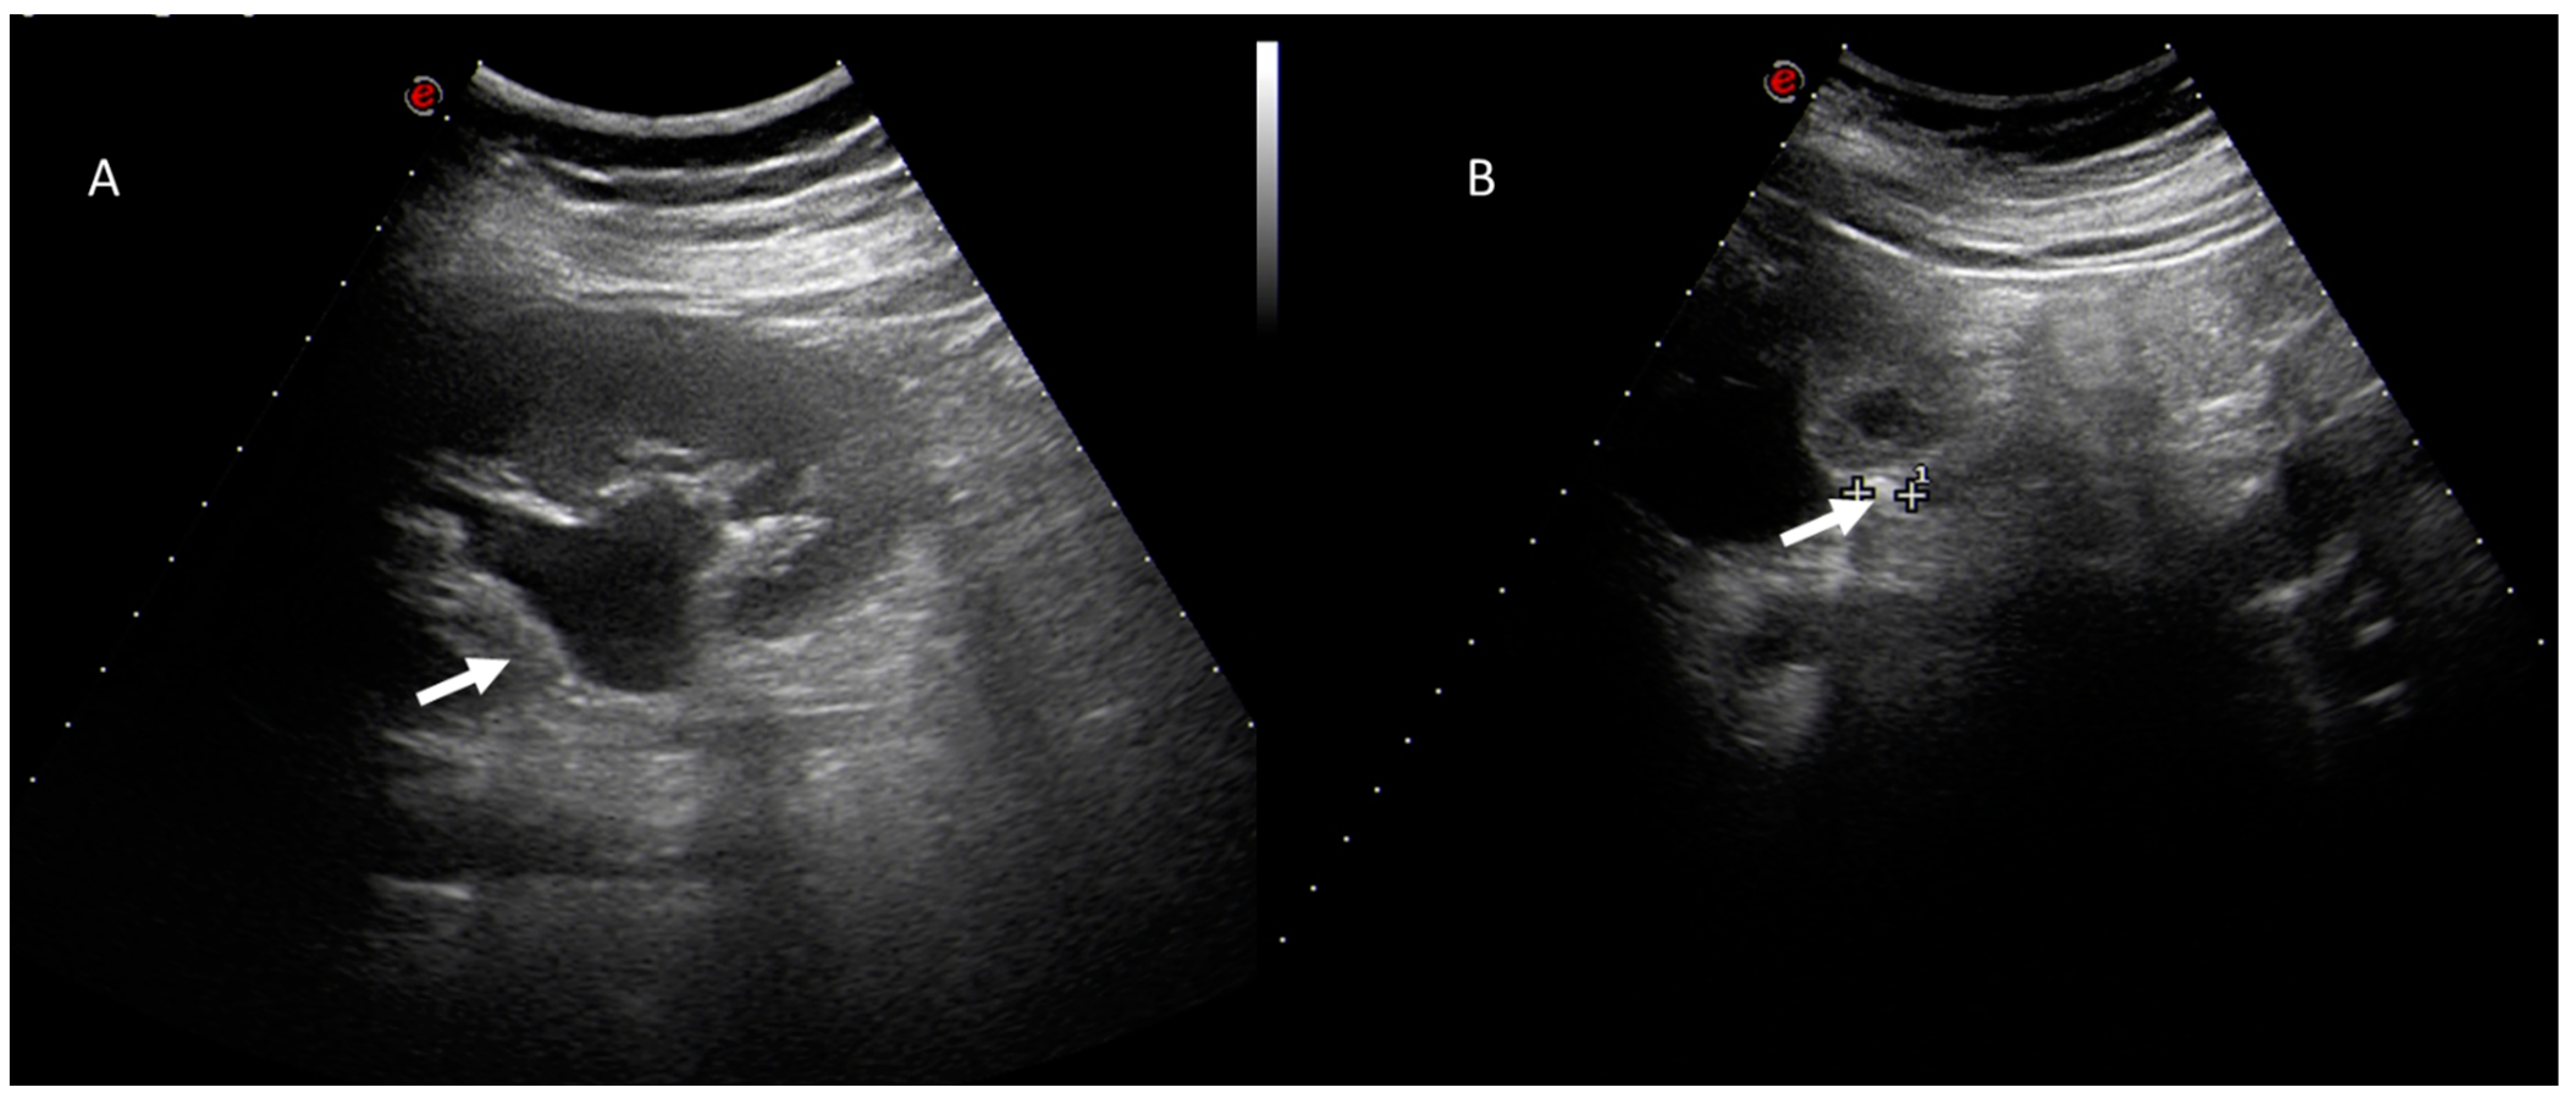

Figure 2.

Pregnant woman with emergency room admission for right abdominal pain and fever. US assessment (A,B) shows (arrows) thickening of the gallbladder walls, with intraluminal hyperechoic material.